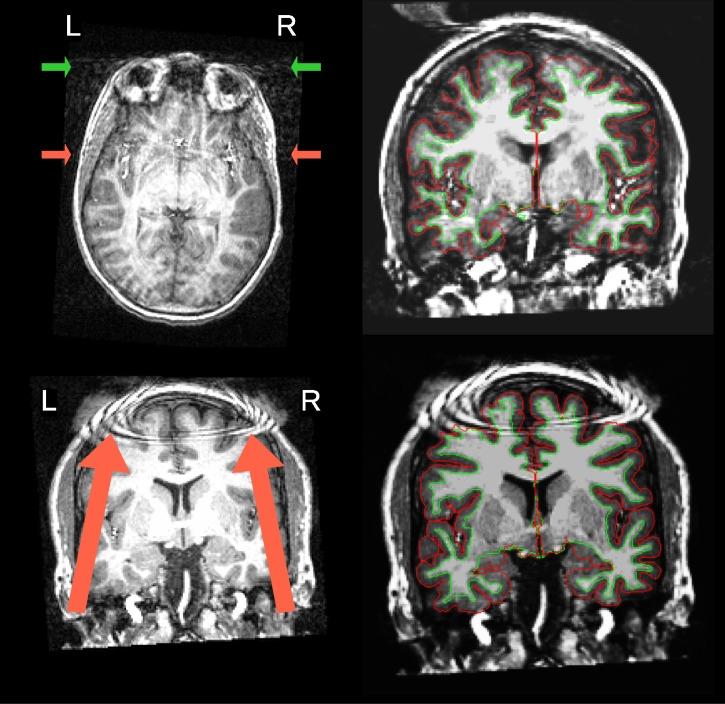

Quality control of MRI is essential for excluding problematic acquisitions and avoiding bias in subsequent image processing and analysis. Visual inspection is subjective and impractical for large scale datasets. Although automated quality assessments have been demonstrated on single-site datasets, it is unclear that solutions can generalize to unseen data acquired at new sites. Here, we introduce the MRI Quality Control tool (MRIQC), a tool for extracting quality measures and fitting a binary (accept/exclude) classifier. Our tool can be run both locally and as a free online service via the OpenNeuro.org portal. The classifier is trained on a publicly available, multi-site dataset (17 sites, N = 1102). We perform model selection evaluating different normalization and feature exclusion approaches aimed at maximizing across-site generalization and estimate an accuracy of 76%±13% on new sites, using leave-one-site-out cross-validation. We confirm that result on a held-out dataset (2 sites, N = 265) also obtaining a 76% accuracy. Even though the performance of the trained classifier is statistically above chance, we show that it is susceptible to site effects and unable to account for artifacts specific to new sites. MRIQC performs with high accuracy in intra-site prediction, but performance on unseen sites leaves space for improvement which might require more labeled data and new approaches to the between-site variability. Overcoming these limitations is crucial for a more objective quality assessment of neuroimaging data, and to enable the analysis of extremely large and multi-site samples.

磁共振成像(MRI)的质量控制对于排除有问题的采集以及避免后续图像处理和分析中的偏差至关重要。目视检查具有主观性,对于大规模数据集而言不切实际。尽管已经在单站点数据集上证明了自动化质量评估,但尚不清楚这些解决方案能否推广到在新站点采集的未见数据。在此,我们介绍MRI质量控制工具(MRIQC),这是一种用于提取质量指标并拟合二元(接受/排除)分类器的工具。我们的工具既可以在本地运行,也可以通过OpenNeuro.org门户作为免费在线服务运行。该分类器在一个公开可用的多站点数据集(17个站点,N = 1102)上进行训练。我们进行模型选择,评估旨在最大化跨站点泛化的不同归一化和特征排除方法,并使用留一站点交叉验证估计在新站点上的准确率为76%±13%。我们在一个保留数据集(2个站点,N = 265)上确认了该结果,准确率同样为76%。尽管训练后的分类器性能在统计学上高于随机水平,但我们表明它易受站点效应影响,无法解释新站点特有的伪影。MRIQC在站点内预测中表现出高精度,但在未见站点上的性能仍有改进空间,这可能需要更多标记数据和针对站点间变异性的新方法。克服这些限制对于更客观地评估神经影像数据以及分析极大型和多站点样本至关重要。